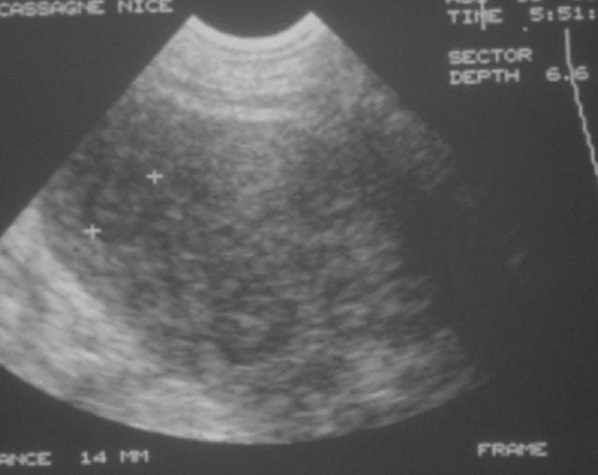

Aspect echographique d'une

lymphome maligne de la rate . La rate est

volumineuse ( slenomegalie ), , composant des

nodules hypoechogene , heterogene de taille variable . On peut en

s'observe image adenopathie hypoechogene

perihilaire , |